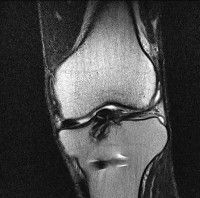

무릎 mri 간단히 봐주실 수 있으시나요 ㅠㅠ

안녕하세요 8년전 십자인대 수술하고 최근 무리한 운동에 무릎 불편감이 생겨서

mri 찍었습니다.

진단결과는 첫 찍은 병원에서 활액막염 이라는 진단을 받았습니다. 혹시 봐주실 수 있으실까요?

올라온 MRI가 단편적이라서 정확한 진단에 어려움이 있지만 십자인대에는 큰 이상이 있지는 않은것 같으며, 무릎관절내 물이 있는 것으로 보아 활액막염의 진단이 맞을 것 같습니다.

하지만 단편적인 영상이기 때문에 촬영병원에서 정확한 판독지 등을 받으시는 것이 좋겠습니다.